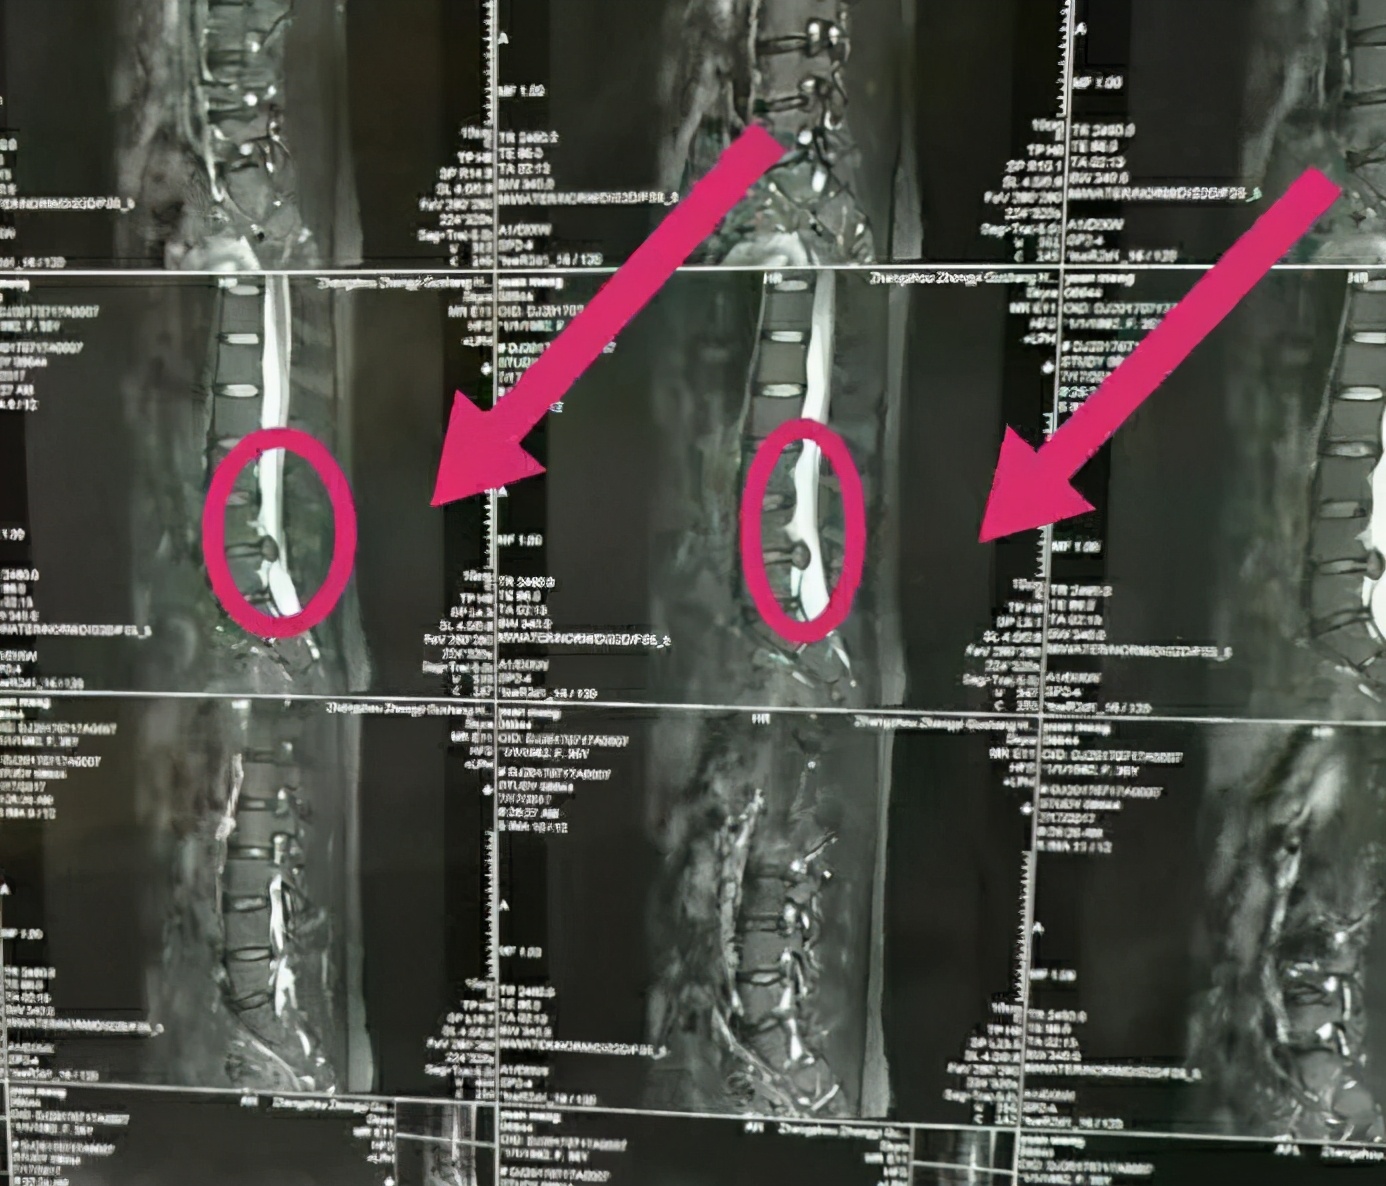

西安市某中学王老师觉得腰部僵痛,刚开始她以为是批改作业劳累所致,便自行购买膏药贴敷。这几天随着气温走低,王老师的腰痛已由腰部放射至腿部,一节课四十五分钟的站立就让她疼痛难忍,于是便来到西安市中医医院针灸推拿康复科安军明主任医师门诊就诊,经过腰部CT检查,王老师确诊患了腰椎间盘突出症。